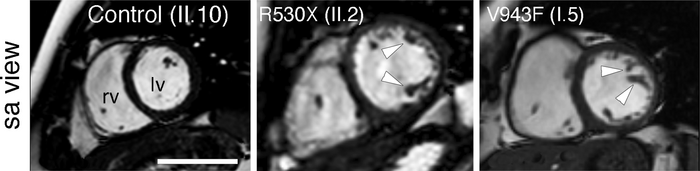

Cardiac magnetic resonance images from a healthy family member (left) and two patients with non-compaction cardiomyopathy (center and right). Arrowheads mark the trabeculae characteristic of the disease.